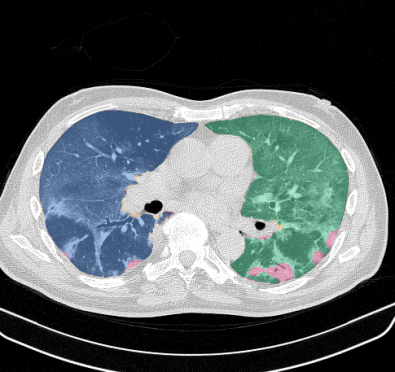

Lung segmentation results for the polymorphic and nonpolymorphic models are shown in Figure 3. Quantitative evaluation of lung segmentations was performed on CT images by comparing the segmentations to ground truth manual segmentations. The Dice coefficient was used to measure volume overlap and the average symmetric surface distance (ASSD) was used to assess boundary accuracy. The ASSD and Dice coefficient results for each of the four evaluation datasets are shown in Table 2. Overall, on the COVID-19 dataset the polymorphic model achieved an average ASSD of mm and average Dice coefficient of . By comparison, the nonpolymorphic model achieved an average ASSD of mm and average Dice coefficient of . ASSD and Dice coefficient results with respect to nonaerated lung volume fraction are displayed in Figure 4. Two-way analysis of variance revealed a significant interaction between model and nonaerated fraction for each evaluation metric, indicating that the regression coefficients with respect to nonaerated fraction were significantly different for polymorphic vs. nonpolymorphic models.